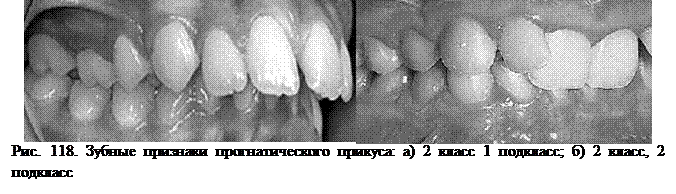

Первый подкласс II класса характеризуется веерообразным наклоном передних зубов верхней челюсти и сужением зубных рядов в боковых отделах.

Второй подкласс II класса – характеризуется небным наклоном верхних резцов. Такой наклон имеют только центральные резцы, а боковые резцы очень часто отклонены в сторону губы и повернуты по оси.

В отличие от первой разновидности при этой форме прогнатического прикуса, сагиттальная щель между верхними и нижними передними зубами, как правило, отсутствует.

При осмотре полости рта отмечается мезиальное расположение верхних зубов, веерообразный наклон передних зубов верхней челюсти и сужение зубных рядов в боковых отделах.

Пациенты имеющие второй подкласс II класса – имеют характерный небный наклон верхних резцов. Такой наклон имеют только центральные резцы, а боковые резцы очень часто отклонены в сторону губы и повернуты по оси.

Характерным клиническим признаком второго подкласса II класса прогнатического прикуса, является также наличие клинических признаков глубокого блокирующего прикуса.